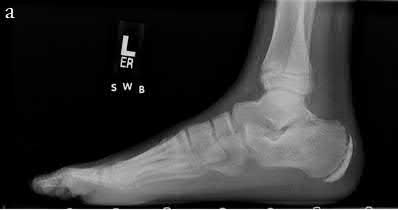

Question 29

A 32-year-old male falls from a ladder and sustains a Hawkins Type III fracture of the talar neck. By definition, a Hawkins Type III injury involves a talar neck fracture accompanied by which of the following patterns of dislocation?

Explanation

The Hawkins classification describes talar neck fractures: Type I is nondisplaced; Type II involves subtalar subluxation or dislocation; Type III involves dislocation of both the subtalar and tibiotalar (ankle) joints (the talar body extrudes posteromedially); Type IV (added by Canale) involves dislocation of the subtalar, tibiotalar, and talonavicular joints. The risk of avascular necrosis (AVN) increases substantially with each grade, approaching 100% in Type III/IV if not reduced urgently.